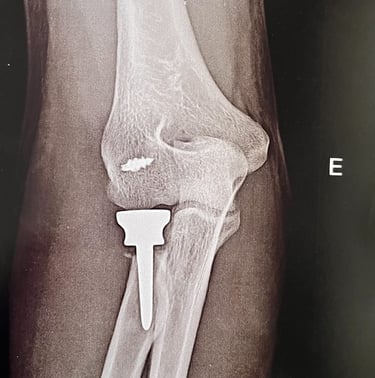

Patologias do Cotovelo

Tratamento de epicondilite lateral (cotovelo de tenista), lesões de tendões, instabilidades e outras afecções da articulação do cotovelo.